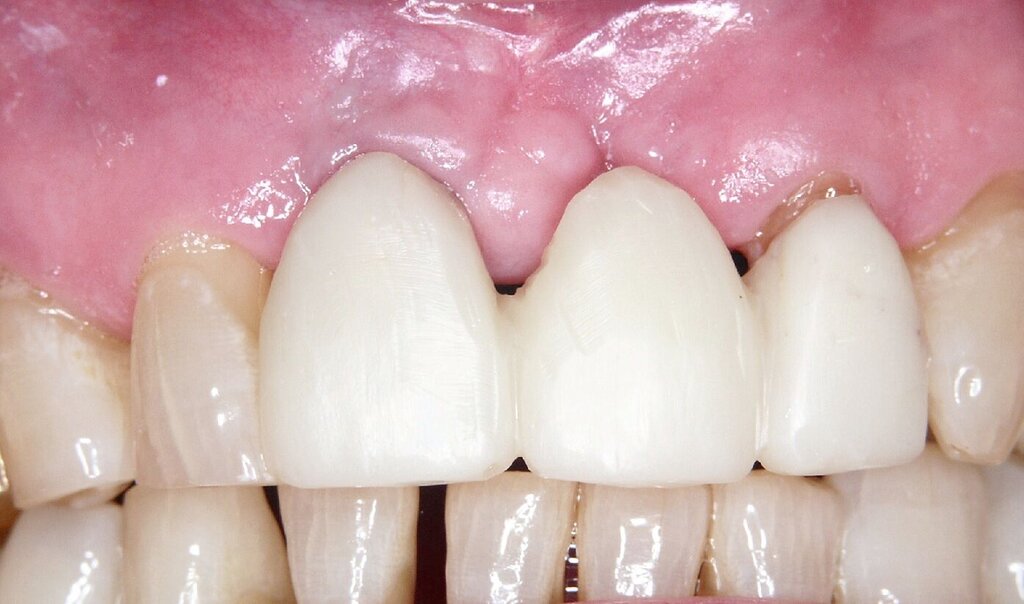

Bei einem 76-jährigen Patienten wurde ein circa 20 Jahre altes Aluminiumoxid-Implantat (Abb. 2a) entfernt, nachdem die ausgeprägte Gingivarezession in Kombination mit dem Abbau der vestibulären Knochenlamelle keine ausreichende Mundhygiene mehr zuließ. Nach Entfernung der Krone auf dem intakten Implantat in regio 11 konnte zur provisorischen Lückenversorgung eine stuhlgefertigte, kombiniert Zahn/Implantat-gestützte Brücke von 011 auf 22 eingegliedert werden (Abb. 2b). Eine Nachimplantation war aufgrund der günstigen Prognose für den Pfeilerzahn 22 überflüssig. Das verbliebene Weichgewebsdefizit wurde drei Monate nach der Explantation mit einem Bindegewebstransplantat vom harten Gaumen kompensiert (Abb. 2c bis 2e). Nach einer Konsolidierungsphase von weiteren drei Monaten wurde das Provisorium durch eine monolithische Zirkoniumdioxidbrücke mit ausschließlich vestibulärer Verblendung ersetzt (Abb. 2g). Eine invasive knöcherne Augmentation mit Wiederherstellung des knöchernen Kieferkamms nach dem Implantatverlust in regio 21 konnte vermieden werden, da eine erneute Implantation für das Behandlungsziel einer festsitzenden Versorgung nicht nötig war.